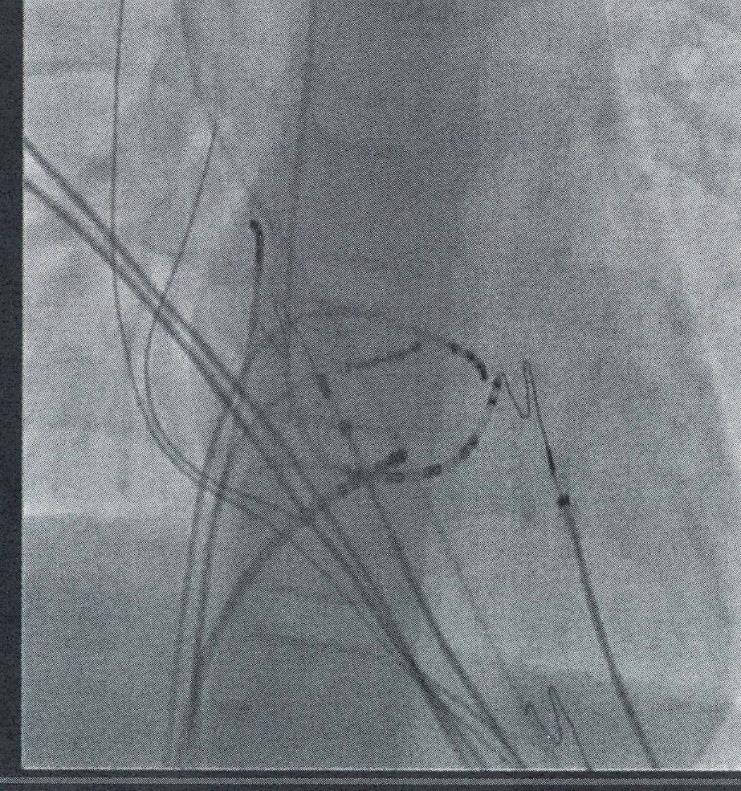

Διουρηθρική εκτομή (transurethral resection of the bladder tumour, TURBT). Συνιστά δι αγνωστική και δυνητικά θεραπευτική μέ θοδο, αφού στοχεύει αφενός στην εκτομή όλων των ορατών όγκων, αφετέρου στη σταδιοποίηση της νόσου. Είναι αναγκαία η πλήρης εξαίρεση του όγκου καθώς και τμήματος του μυϊκού τοιχώματος ώστε να είναι δυνατή η ιστολογική διαπίστωση ενδε χόμενης διήθησης. Σε περίπτωση ατελούς εκτομής, απουσίας εξωστήρα μυός στο πα θολογικό δείγμα – που μπορεί να οδηγήσει σε υποσταδιοποίηση – ή υψηλού κινδύνου νόσου Ta ή T1, συνίσταται η επανάληψη του TURBT εντός 4 έως 6 εβδομάδων. Η ποι ότητα της τεχνικής επηρεάζει τα κλινικά αποτελέσματα. Ενδεικτικά, μια μελέτη κο όρτης σε 1.865 ασθενείς που υποβλήθηκαν σε TURBT διαπίστωσε ότι η υποσταδιοποί ηση κατά την εκτομή συσχετίζεται με χα μηλότερη ειδική για τον καρκίνο επιβίωση [αναλογία κινδύνου (hazard ratio, HR) 1,48, 95% διάστημα εμπιστοσύνης (confidence interval, CI) 1,00-2,18]. ⊲ Κυτταρολογική εξέταση ούρων. Μέσω αυ τής διαπιστώνεται η ύπαρξη καρκινικών κυττάρων στα ούρα. Στηρίζεται στη χαμηλή συνοχή που παρουσιάζουν τα καρκινικά κύτταρα – ιδιαίτερα εκείνα που προέρχο νται από όγκους υψηλού βαθμού κακοήθει ας – με επακόλουθες την αποφολίδωση και ανίχνευση τους στα ούρα. Η κυτταρολογική εξέταση χρησιμοποιείται επικουρικά κατά τη διάγνωση για την ανίχνευση όγκου υψη λής κακοήθειας καθώς και του CIS. Επιπλέ ον, χρησιμεύει στην παρακολούθηση της νόσο μεταθεραπευτικά. ⊲ Απεικονιστικές μέθοδοι. Για τη διάγνωση όγκων του ανώτερου ουροποιητικού χρη σιμοποιείται αξονική ουρογραφία ή εναλλα κτικά ενδοφλέβια ουρογραφία. Σε ασθενείς με επιβεβαιωμένο μυοδιηθητικό καρκίνο, η ύπαρξη μεταστάσεων ανιχνεύεται με τη χρήση αξονικής (computed tomography, CT) ή μαγνητικής (magnetic resonance imaging, MRI) τομογραφίας θώρακος, κοιλίας και πυ έλου. ⊲ Μοριακή διάγνωση. Ογκογόνες μεταλλαγές (πχ. στο γονίδιο FGFR2/3) ή έκφραση βιοδει κτών ανταπόκρισης στην ανοσοθεραπεία (πχ. PD-L1) διερευνώνται στα πλαίσια της

Διαχείριση και θεραπευτικές προσεγγίσεις3,9,10,12 ΜΗ-ΜΥΟΔΙΗΘΗΤΙΚΟ ΟΥΡΟΘΗΛΙΑΚΟ ΚΑΡΚ Ι Ν Ώ ΜΑ Η κύρια θεραπευτική προσέγγιση για το μη-μυοδιηθητικό καρκίνωμα περιλαμβάνει τη διουρηθρική εκτομή (TURBT) ακολουθούμε νη από επικουρική ενδοκυστική θεραπεία με σκοπό τη μείωση των υποτροπών της νόσου: ⊲ Μετεγχειρητική έγχυση χημειοθεραπείας με μιτομυκίνη C, επιρουμπικίνη ή δοξο ρουμπικίνη. Χρησιμοποιείται για χαμηλού κινδύνου ή για επιλεγμένους ενδιάμεσου κινδύνου όγκους. Μία μετα-ανάλυση 7 τυ χαιοποιημένων κλινικών μελετών, έδειξε ότι η ενδοκυστική χημειοθεραπεία μειώνει κατά 39% την πιθανότητα υποτροπής στα επόμενα 3,4 έτη (απόλυτη μείωση από 48% έως 37%). Ωστόσο, δεν υπάρχουν δεδομένα για τη διαφορά στην αποτελεσματικότητα μεταξύ αυτών των φαρμάκων (μιτομυκίνη C, επιρουμπικίνη, δοξορουμπικίνη)

Σε ασθενείς με χαμηλού κινδύνου όγκους, μετά τη διουρηθρική εκτομή, η ενδοκυστική χημειοθεραπεία πραγματοποιείται οριστικά προκειμένου να μειώσει το ποσοστό υπο τροπής. Για τους ασθενείς με ενδιάμεσου κινδύνου όγκους επιλέγεται είτε επαναλαμ βανόμενη ενδοκυστική χημειοθεραπεία είτε ανοσοθεραπεία με BCG για 1 έτος. Στους ασθενείς αυτούς, η ενδοκυστική θεραπεία, παρ’ ότι επιμηκύνει την περίοδο χωρίς υπο τροπή, τελικά δεν αποτρέπει την εξέλιξη της νόσου. Ασθενείς με υψηλού κινδύνου όγκους συνήθως υποβάλλονται σε δεύτερη TURBT και εν συνεχεία σε ανοσοθεραπεία με BCG για 3 έτη. Επειδή το CIS δεν μπορεί να αφαιρεθεί με TURBT, οι ασθενείς με CIS υποβάλλονται απευθείας σε ενδοκυστική ανοσοθεραπεία για 3 έτη. Σε γενικές γραμ μές, η έκβαση της θεραπείας έχει ευνοϊκούς δείκτες επιβίωσης: ενδεικτικά, σύμφωνα με την Αμερικανική Ουρολογική Εταιρεία (American Urological Association, AUA), τα ποσοστά πενταετούς επιβίωσης για τη χωρίς υποτροπή και τη χωρίς εξέλιξη νόσο ανέρχονται αντιστοίχως σε 43% και 93% για όγκους χαμηλού κινδύνου, 33% και 74% για όγκους ενδιάμεσου κινδύνου και 23% και 54% για όγκους υψηλού κινδύνου. Παρ’ όλα αυτά, καθίσταται προφανές ότι ο κίνδυνος υποτροπών είναι υψηλός ανεξαρτήτως του βαθμού κινδύνου. Επιπλέον, ο κίνδυνος εξέ λιξης της νόσου είναι σημαντικός, ιδιαίτερα στους υψηλού κινδύνου όγκους. Με βάση αυτά τα δεδομένα, όλοι οι ασθενείς παρακο λουθούνται τακτικά με κυστεοσκόπηση, ενώ οι ασθενείς με υψηλού κινδύνου όγκους υπο βάλλονται επιπλέον σε κυτταρολογικές εξε τάσεις ούρων και σε αξονική ή ενδοφλέβια

ΜΥΟΔΙΗΘΗΤΙΚΟ ΚΑΡΚ Ι Ν Ώ ΜΑ ΤΗΣ ΟΥΡΟΔΟΧΟΥ Κ Υ ΣΤΗΣ Η θεραπευτική αντιμετώπιση του μυο διηθητικού καρκινώματος της ουροδόχου κύστης καθορίζεται από τον εντοπισμό ή όχι του όγκου καθώς και την ύπαρξη μετα στάσεων. Συνήθως απαιτείται η σύμπραξη ογκολόγων, ακτινολόγων και ουρολόγων προκειμένου να αποφευχθεί ο κατακερμα τισμός της φροντίδας του ασθενούς.

θεραπείας ⊲ Ριζική κυστεκτομή. Αποτελεί την καθι ερωμένη θεραπευτική προσέγγιση για

διηθητικούς όγκους περιορισμένους στην ουροδόχο κύστη. Όγκοι με υποψία μετάστασης στους επιχώριους λεμφαδέ νες (Ν1) είναι επίσης επιλέξιμοι για ριζική κυστεκτομή αφού προηγηθεί εισαγωγική χημειοθεραπεία. Χρησιμοποιείται επίσης σε μη-μυοδιηθητικούς όγκους υψηλού κινδύνου που υποτροπιάζουν ή δεν αντα ποκρίνονται στην ενδοκυστική ανοσοθε ραπεία. Τέλος, ασθενείς με προχωρημένη ή μεταστατική νόσο μπορούν να υποβλη θούν σε παρηγορητική κυστεκτομή για την ανακούφιση από συμπτώματα (πχ. επώδυνη αιματουρία) και τη βελτίωση